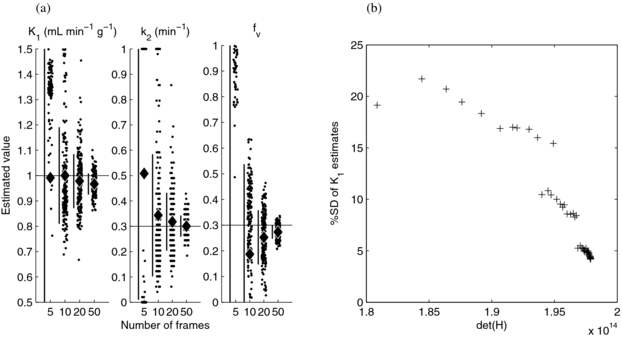

To investigate the correspondence of det(H) and the precision of the flow estimate, MC simulation was performed for the a subset of the most promising schedules. Figure 5(a) shows that the optimal five-frame schedule performed poorly, thus resulting in a wide and non-normal distribution of parameter estimates, and that the optimal 10, 20 and 50 frame schedules performed progressively better, with estimates clustered closer to the true parameter values with a larger number of frames. We expanded the analysis using a larger number of schedules, selected the 44 schedules with the highest det(H) for each total number of frames from 17 to 60, and constructed a scatter plot of the precision of the K1 estimate versus det(H) (figure 5(b)). This demonstrated that the standard deviation of K1 estimates decreased with increasing det(H) and thus provided evidence that det(H) is a valid predictor of estimate precision and appropriate for use in experiment design.

Figure 5. Simulation results for the D-optimal schedules. Parameter estimates using 5, 10, 20 and 50 frame schedules (a). Each column shows individual results as points (for visual clarity, a randomly selected subset is shown), the estimates' mean (diamond) and ±SD (vertical bar); the horizontal lines show the true parameter values. Standard deviation of the K1 estimates versus det(H) for 44 schedules (b).